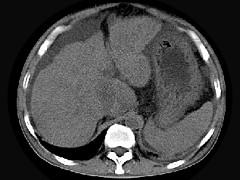

问题 男,44岁,有乙肝病史,现腹胀,右上腹痛,消化不良,消瘦、乏力、贫血、黄疸,血清转氨酶升高,白蛋白/球蛋白比值倒置。CT、MRI检查如下图,最准确的诊断是 ( )

选项 A.肝硬化并腹水 B.肝硬化并腹水、再生结节 C.肝硬化腹水、肝癌 D.肝硬化并再生结节 E.肝硬化并腹水、脂肪肝

答案 B